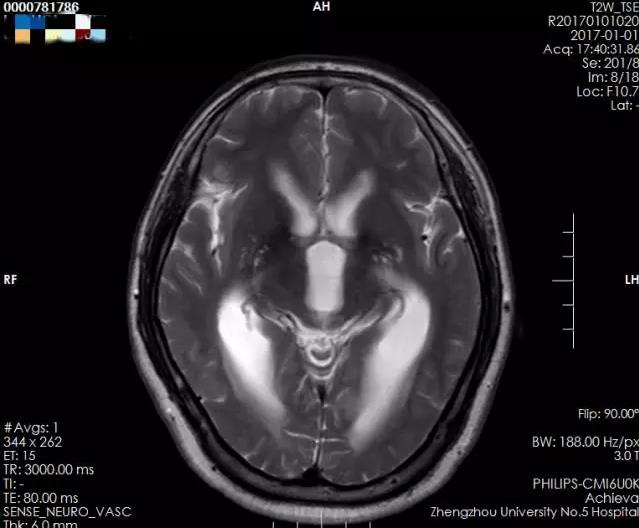

术前侧脑室、三脑室均增大,并有室旁水肿,测量三脑室大小约1.49cm

术后侧脑室及三脑室较前明显缩小,室旁水肿基本消失,测量三脑室大小约1.10cm